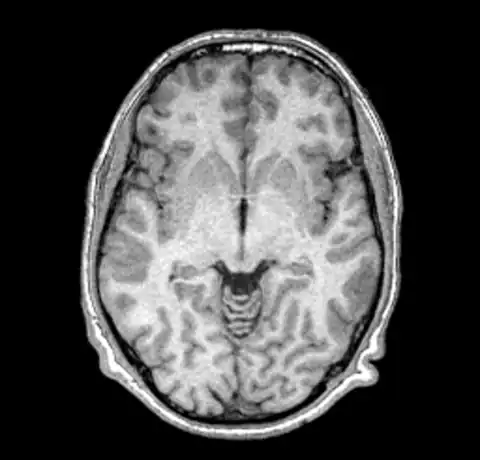

We can now take a look at the corrected file (out.mnc)

As it is very hard to pick the differences between the original and corrected version we can create a field image to visualise the differences.

And then for completeness sake, here are the original and corrected image using a spectral colormap to better visualise the change. Note that in the second (corrected) image the intensity of the white matter is more uniform (the red part).